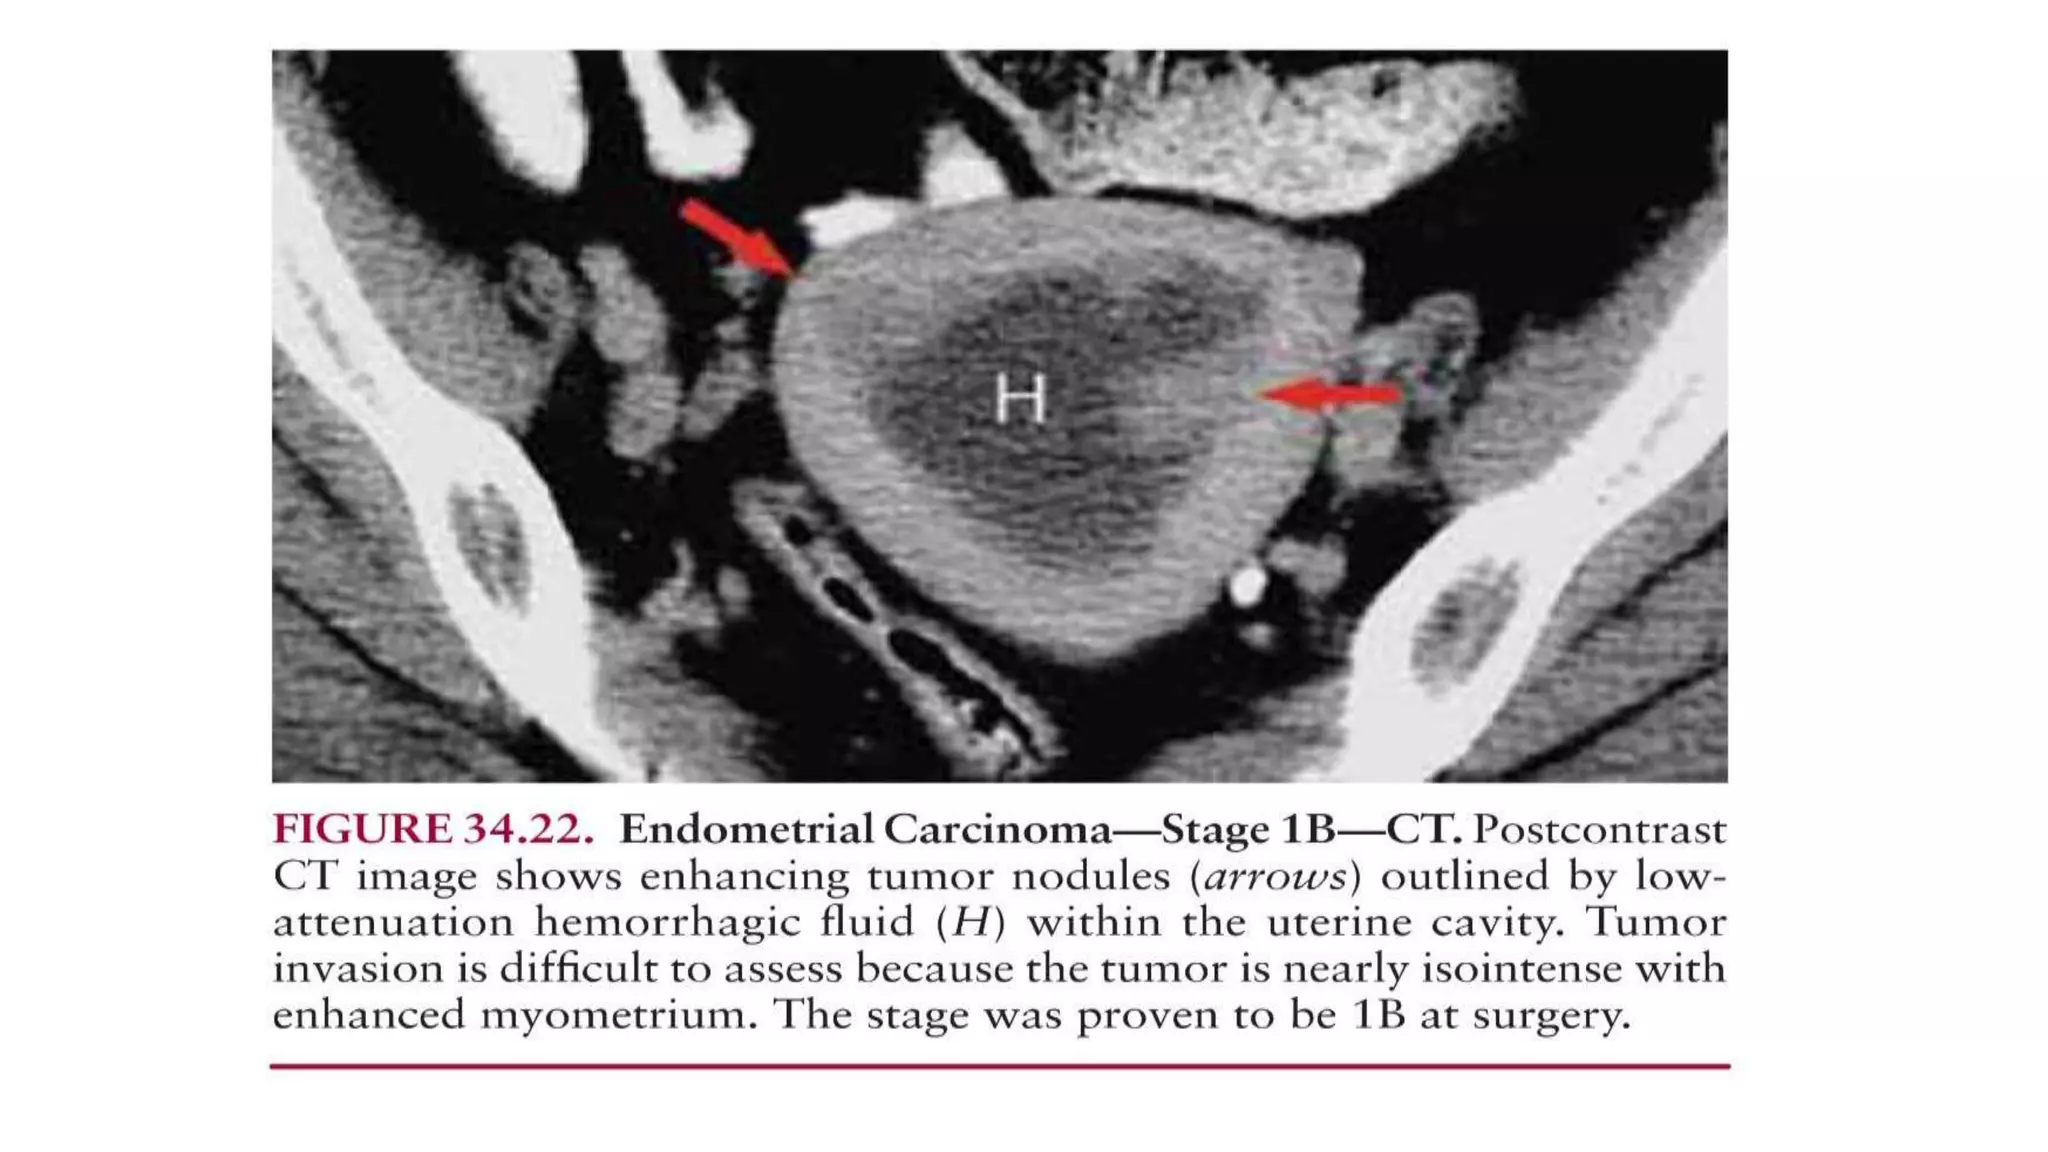

• MRI

• Ideal imaging modality for staging of endometrial Ca.

• An important predictor of lymph node metastases.

• Also allow accurate assessment of more advanced disease such as

cervical stromal invasion or adnexal involvement.

• Contrast-enhanced MRI has been shown to be superior to both in

demonstrating myometrial invasion.

• MRI can also assess cervical extension (stage II) and extrauterine

extension (stages III and IV).

• On unenhanced T1-weighted images

-Endometrial cancer is isointense relative to hypointense normal

endometrium.

• On T2-weighted images

-shows heterogeneous intermediate signal intensity relative to

hyperintense normal endometrium.

• Relative to normal myometrium, the tumor is mildly hyperintense on

T2-weighted images.

• At conventional MR imaging, the depth of myometrial invasion is

optimally depicted with T2- weighted sequences.